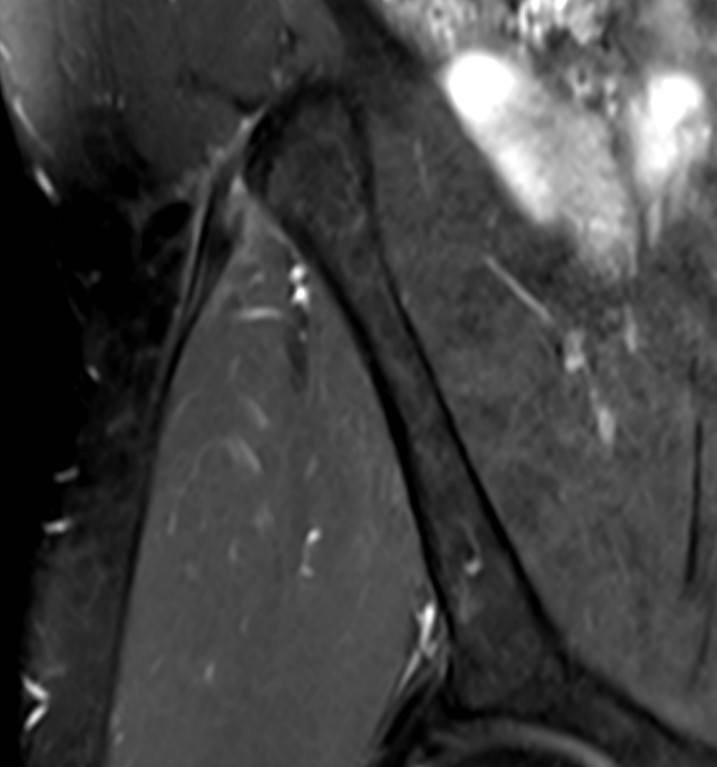

3. Proximal iliotibial band syndrome